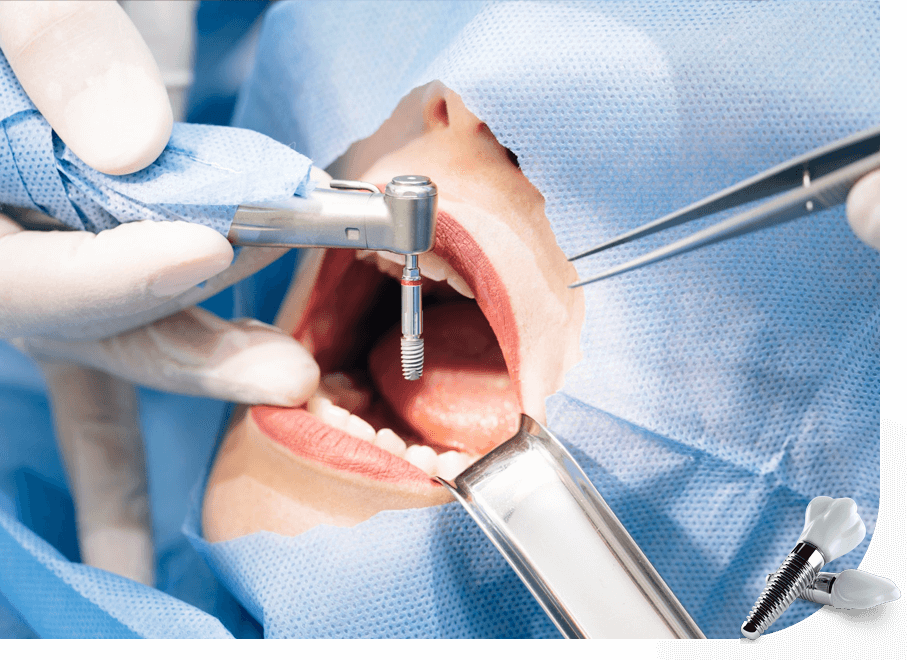

İmplant Diş Tedavisi Nasıl Uygulanır?

Cerrahi müdahaleler ile uygulanan implant tedavisi zor bir süreç olmayıp, alanında uzman doktorlar tarafından gerçekleştirilmesi sonucunda oldukça kolaydır. Buna göre diş implantını uygulama yöntemleri şu şekildedir:

- İmplant tedavisi uygulamalarında öncelikle lokal anestezi ile ilgili alan uyuşturulur.

Uyuşan bölgedeki kemik içerisine implant/implantlar yerleştirilir. Ön diş ya da arka diş olması süreci değiştirebilir. - Uygulama daha önceden çekilmiş bir diş yuvasına yapılacaksa implant için ekstra bir yer açma işlemi uygulanır.

- Yerleşim sırasında küçük bir delik açılarak yerleştirilebileceği gibi diş eti kesilerek de implanta yer açma işlemi uygulanır. Bu adım anestezi altında yapılacağı için herhangi bir acı hissedilmez.